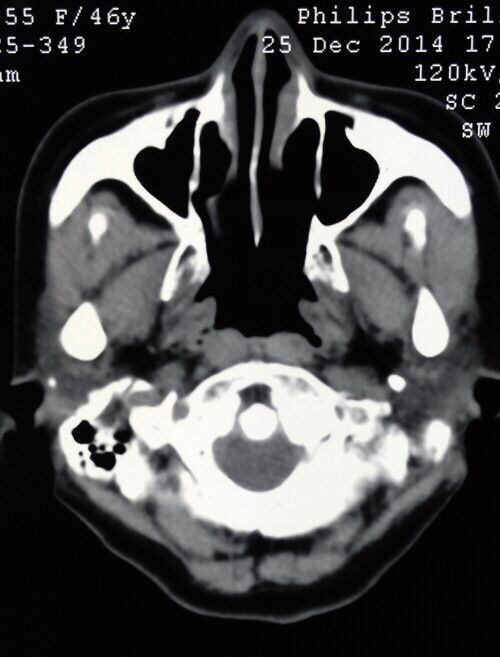

颈椎MRI,CT显示寰枢椎脱位,小脑扁桃体下疝,脊髓空洞